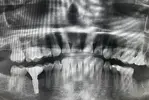

Implant Treatment